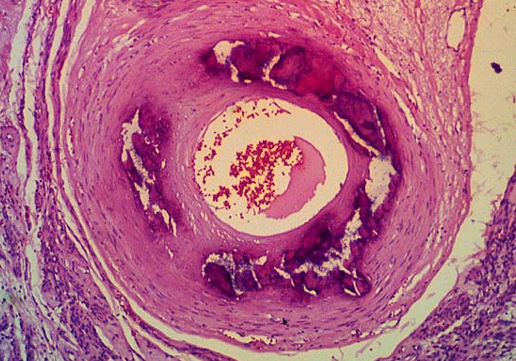

What does this image show?

“Saddle thrombosis” in cat —> occlusion of vessel

“Saddle thrombosis” in dog —> thrombi get longer & extend down iliac arteries

“Saddle thrombosis” in horse —> becomes nidus for further development